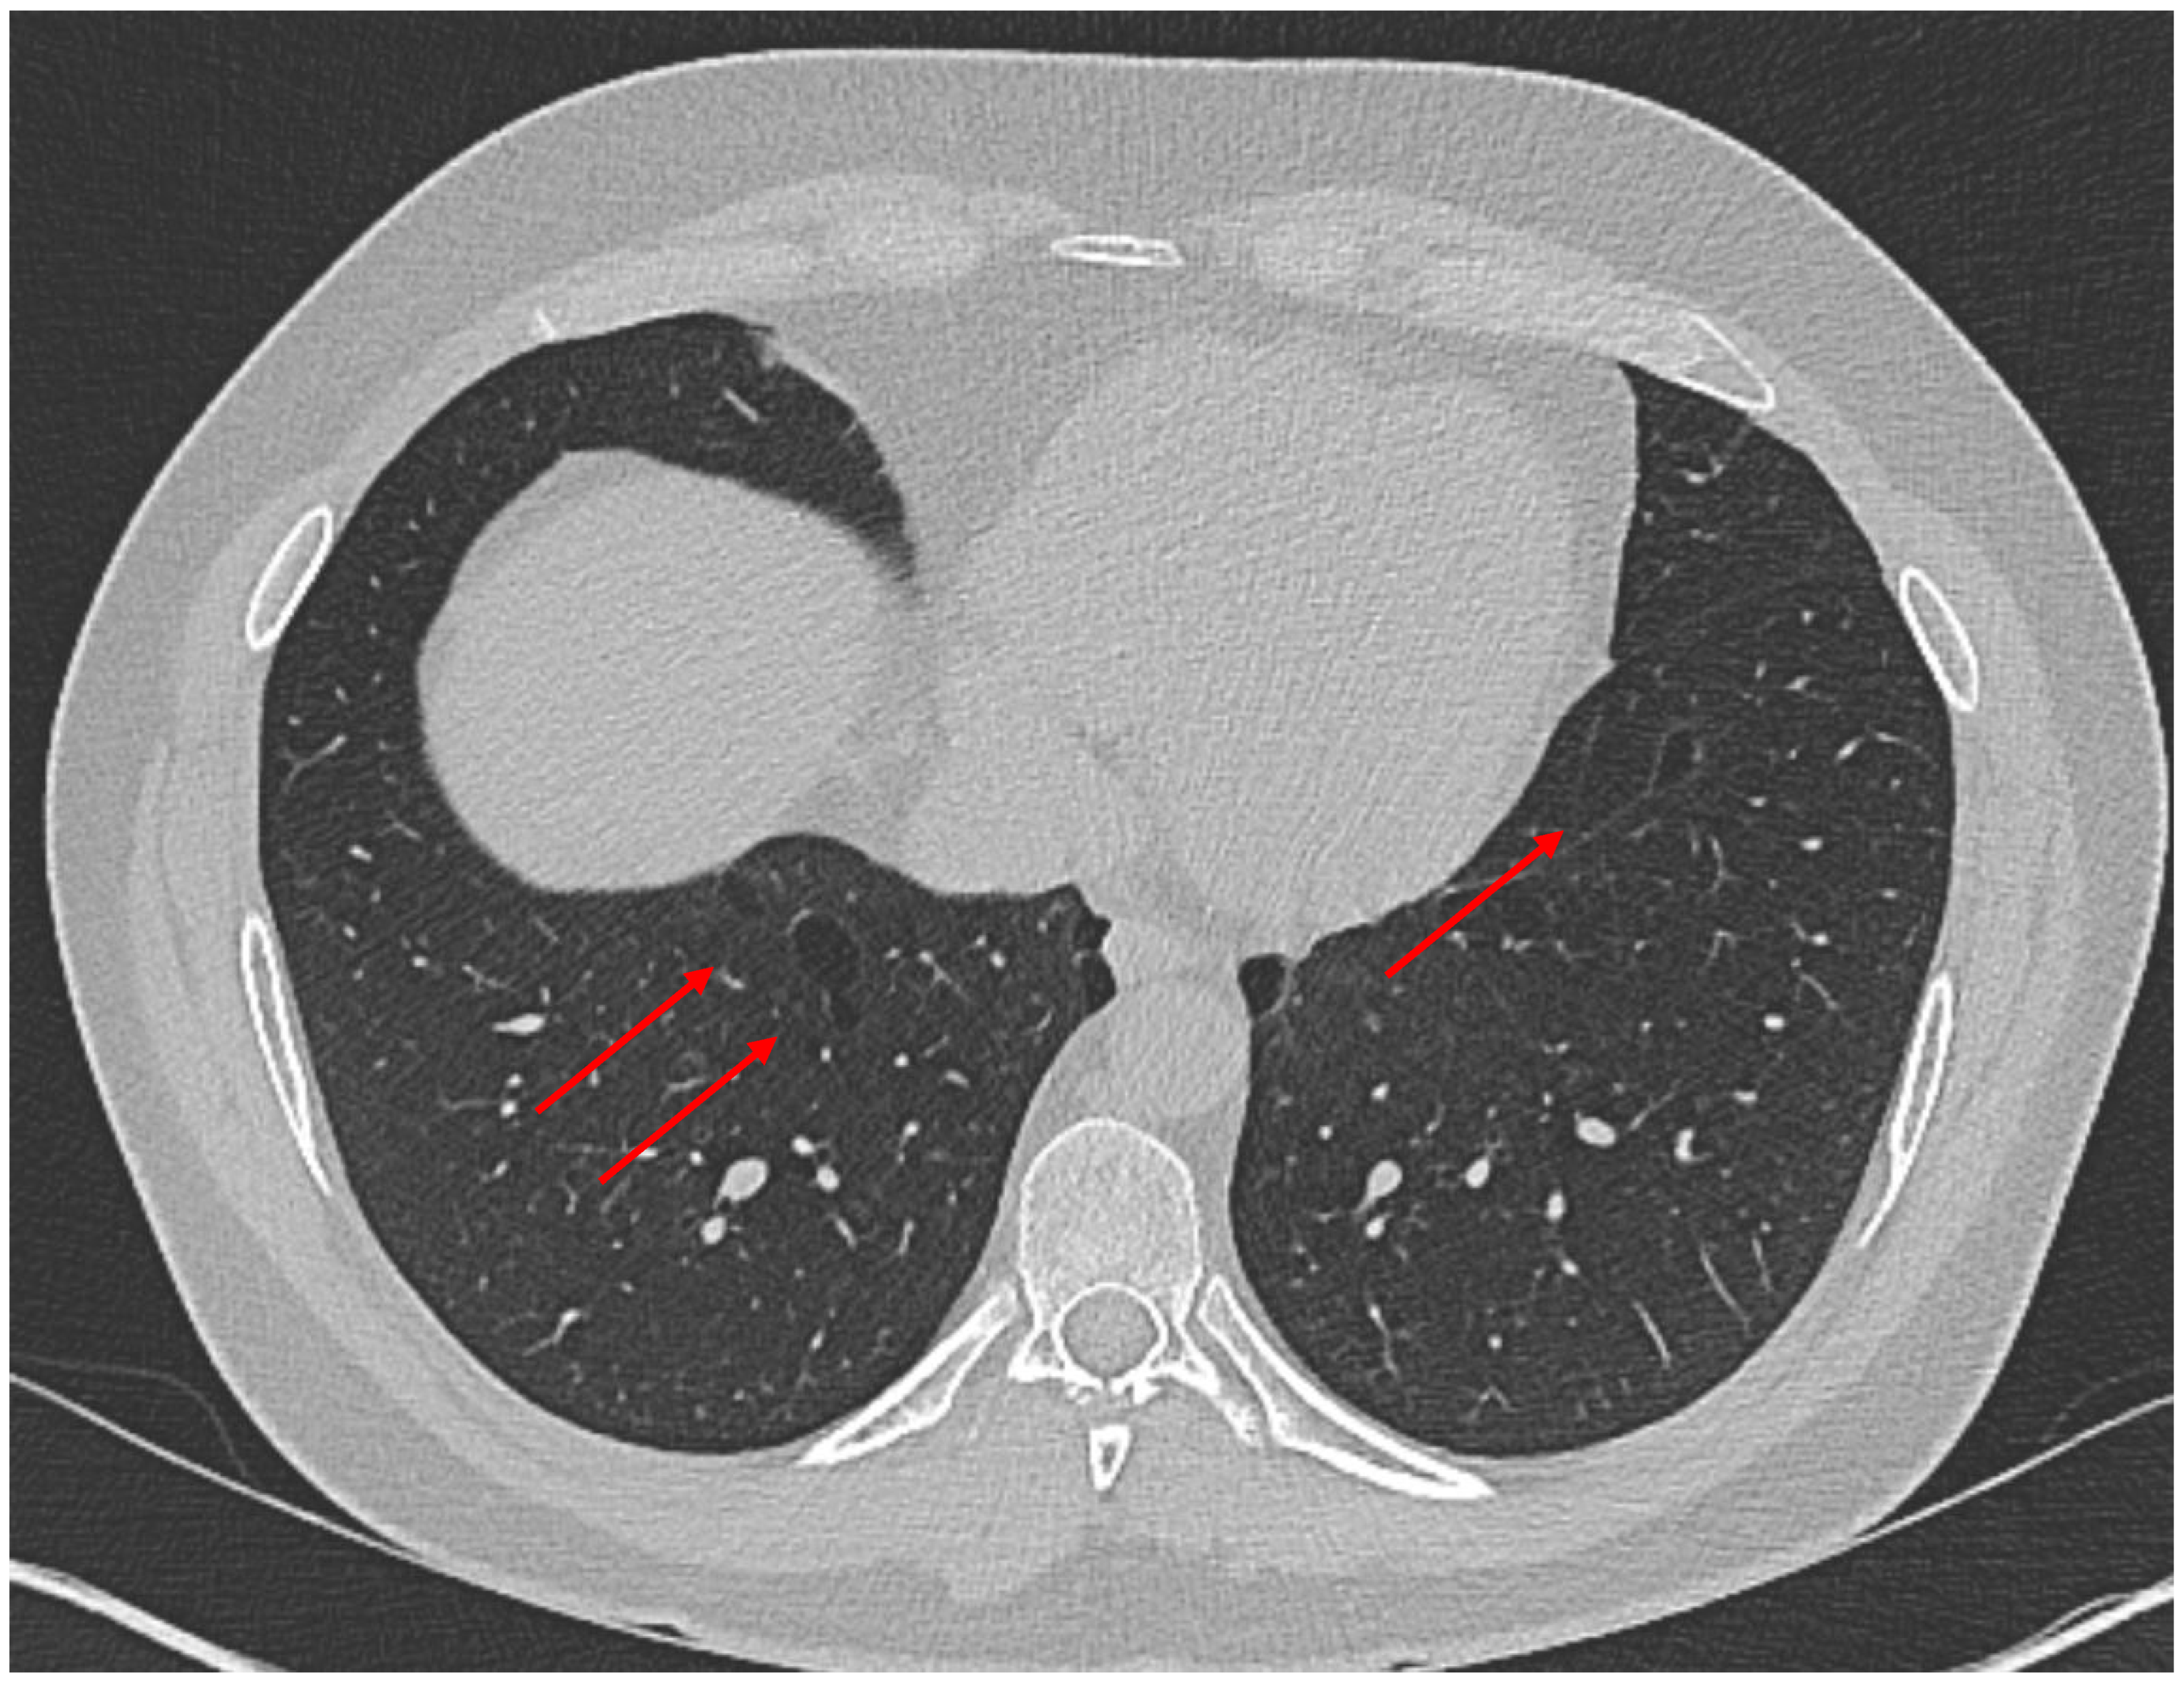

- Narin Tongal, S.; Yilmaz, O.; Ozguven, A.A.; Yuksel, H. DICER1 Syndrome: Coocurrence of Pleuropulmonary Blastoma and Cystic Nephroma. J. Bronchol. Interv. Pulmonol. 2024, 31, 94–97. [Google Scholar] [CrossRef] [PubMed]

- Berber Hamamci, M.; Yesil, S.; Bicakcioglu, P.; Gursoy, T.R.; Agackiran, Y.; Kurucu, B.; Kilci, A.C.; Gok, S.U.; Fettah, A.; Sahin, G. DICER1 syndrome with hepatoblastoma and pleuropulmonary blastoma. Pediatr. Blood Cancer 2024, 71, e31285. [Google Scholar] [CrossRef]

- Thiemann, I.; Hoppen, T.; Laur, M.; Ohlert, M.; Lobitz, S.; Schwerk, N.; Dingemann, J.; Langer, F.; Grychtol, R.M.; Nusslein, T. Complete Tracheal Ring Deformity, Recurrent Pneumothoraces and Pleuropulmonary Blastoma in a Child: Coincidence or Common Genetic Cause? Klin. Padiatr. 2022, 234, 311–313. [Google Scholar] [CrossRef] [PubMed]